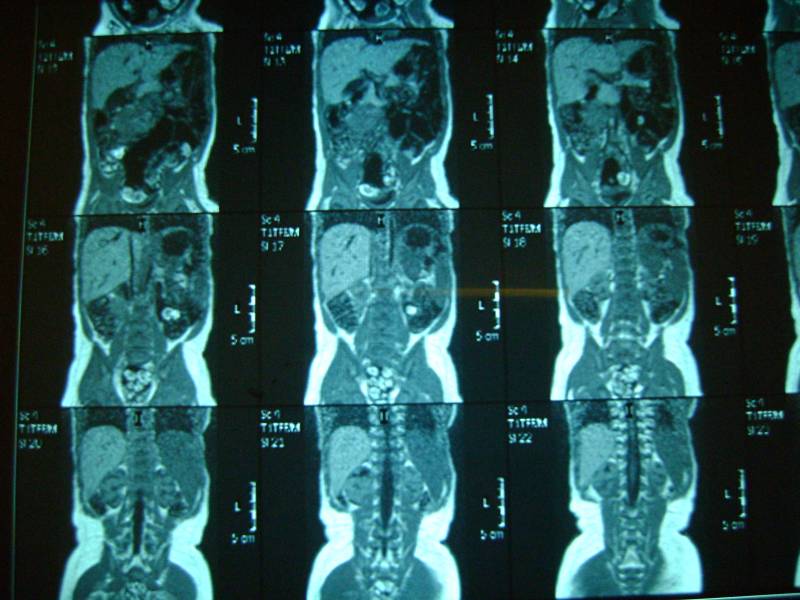

Уважаемый доктор просим посмотреть снимки и нашего сына! Возраст 10 мес. два близнеца однояйцевых у одного поликистоз у второго нет. Можно ли понять тип поликистоза детский или взрослый? Можно ли отправить диск со снимками мрт Вам если можно то куда? К генетикам пойдем в ближайшую среду. Заранее огромное спасибо!!! Попробуем еще фото выложить

Добавляем еще фото